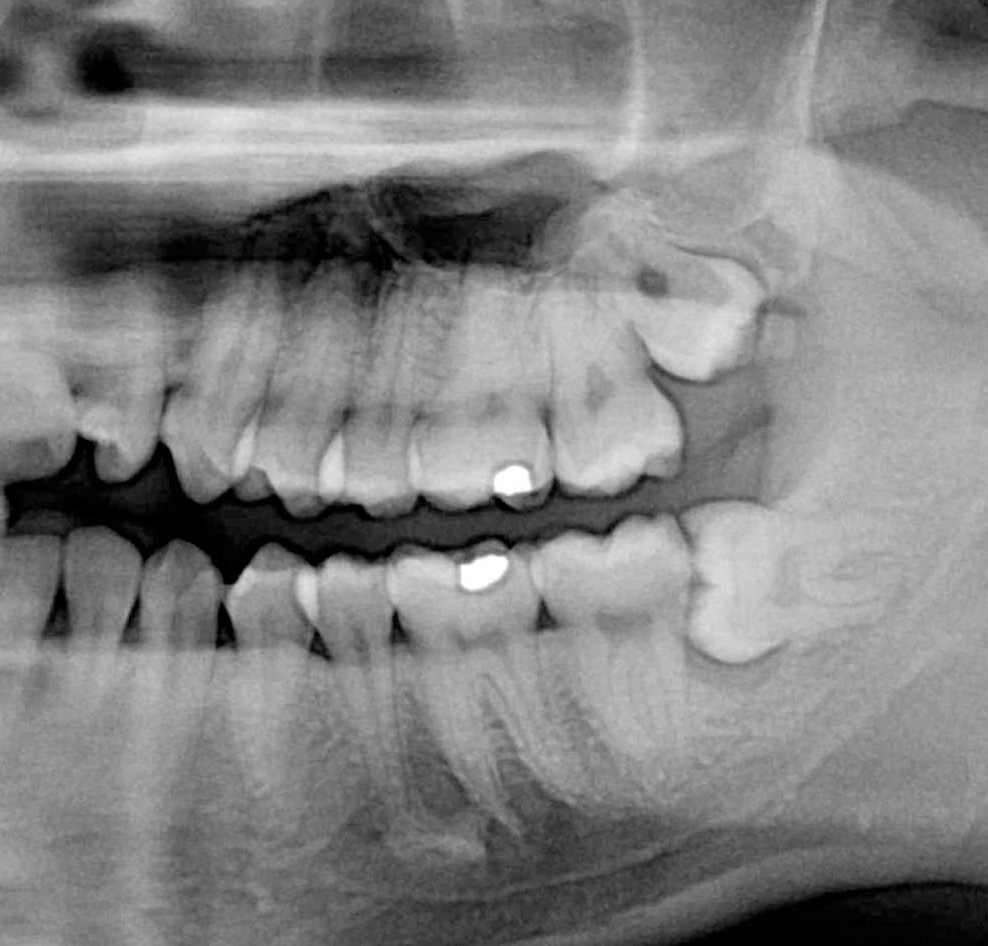

3D DVT - NewTom

Je speciální zubní digitální tříprostorový tomograf (3D), který umožňuje na základě jediného

snímkování vytvořit všechny typy RTG zobrazení, které jsou pro lékaře potřebné. Díky používané technologii tzv. „kuželového paprsku“ a speciálním senzorům je

výrazně zmenšená dávka záření - o více jak 80% proti klasickému CT vyšetření. To je významné zejména u dětí. Pomocí tohoto přístroje je možné zjisti skutečnou situaci v čelistních kostech pacienta tedy množství kosti - můžeme změřit skutečnou šířku i výšku kosti, i kvalitu kosti (hustotu) v místě uvažované implantace. 3D (tříprostorové) zobrazení umožňuje zvýšit prostorovou představu operatéra ještě před vlastní operací a zároveň pacientovi lépe objasnit a ukázat oblast plánovaného zavedení implantátu.

Pacient „neumí číst“ RTG snímky, ale díky 3D zobrazení vidí „svoji skutečnou čelist“

- např. jak je nízká či úzká, vidí průběh nervu nebo velikost čelistní dutiny, což mu umožní i pochopení nutnosti v některých případech provést pomocné zákroky ještě před vlastním zavedením implantátu (viz. kostní štěp, sinus lift, kostní granulát...).

Vyšetření pomocí tohoto přístroje používáme i ve stomatochirurgii (zlomeniny čelistí, zuby moudrosti, cysty, onemocnění čelistního kloubu), ortodoncii (retinované zuby, nadpočetné zuby), parodontologii atd.